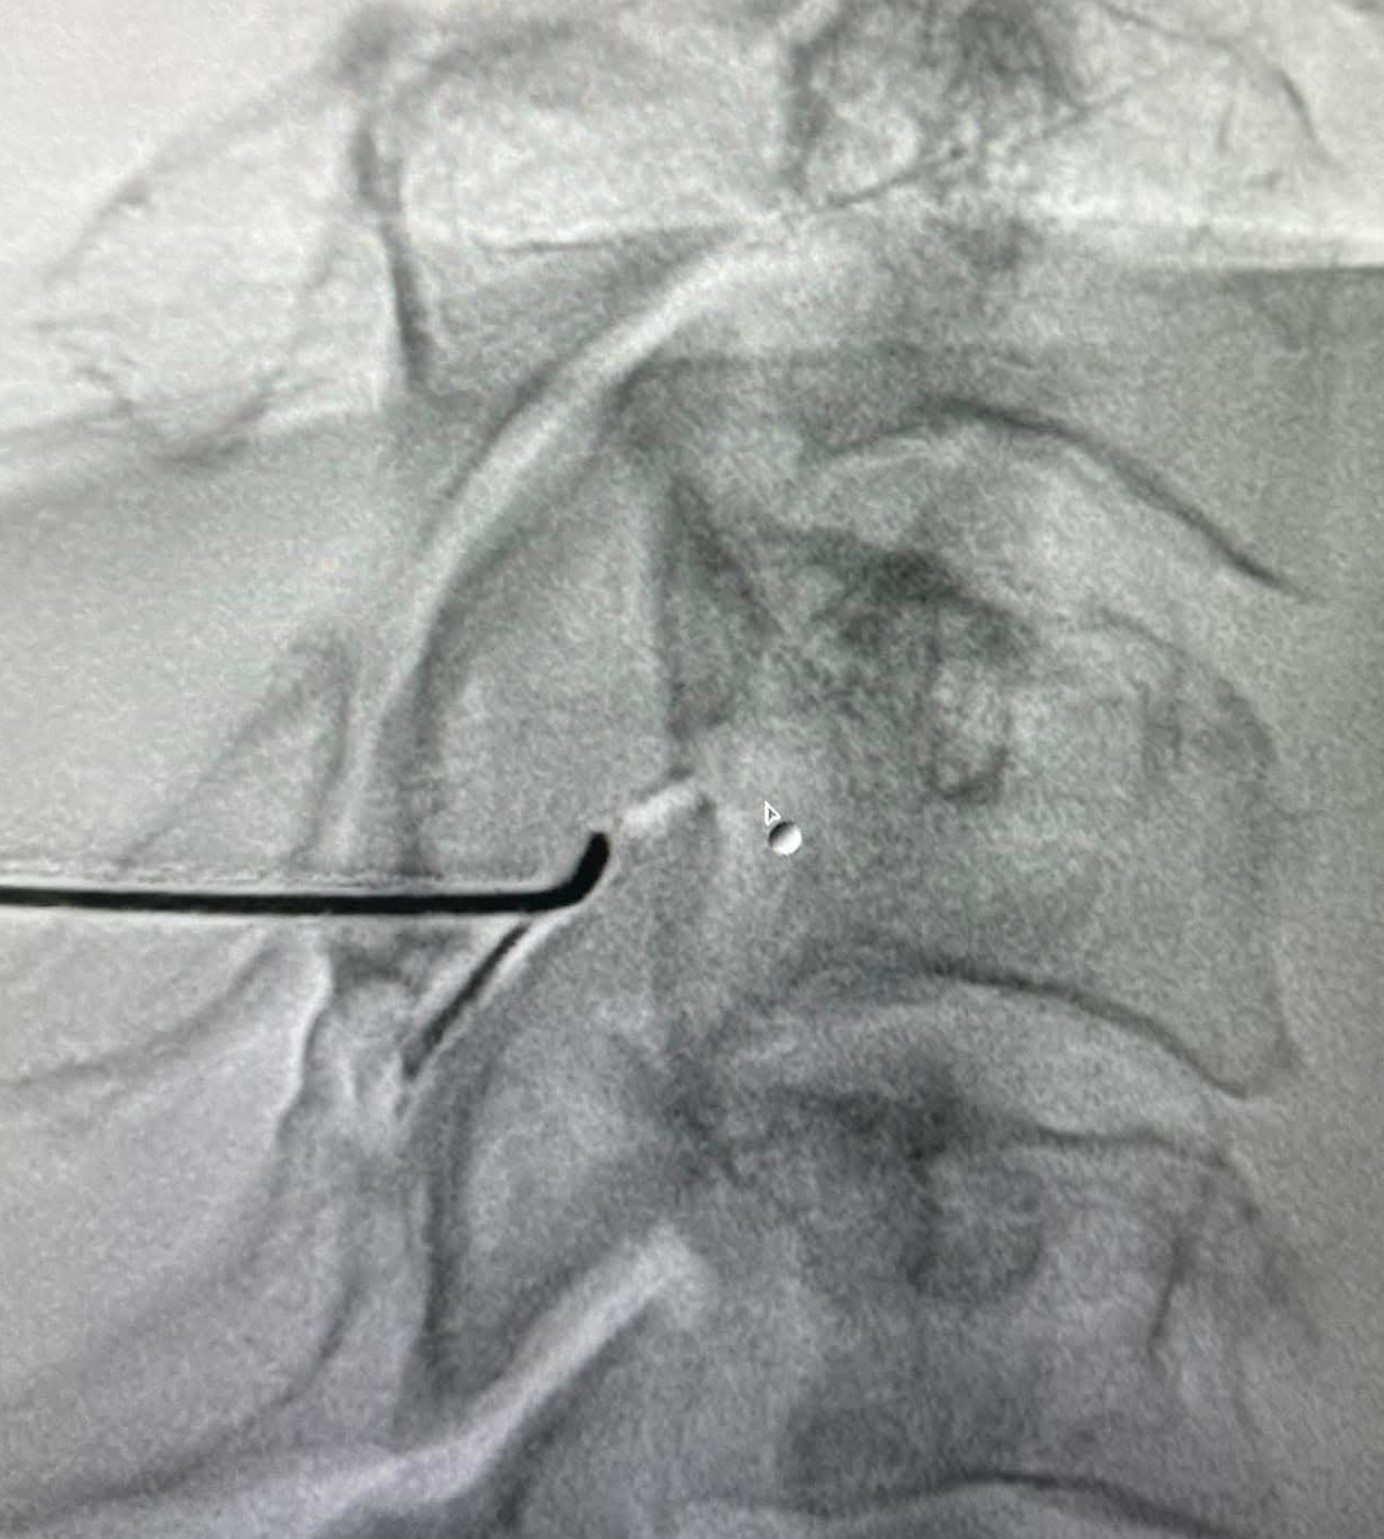

- Εγχύσεις στις αρθρώσεις της αυχενικής μοίρας

- Κατάλυση των αυχενικών αρθρώσεων με χρήση ραδιοσυχνοτήτων

- Επισκληρίδια έγχυση επί υποκείμενης κήλης μεσοσπονδυλίου δίσκου με ή χωρίς ριζιτική προσβολή